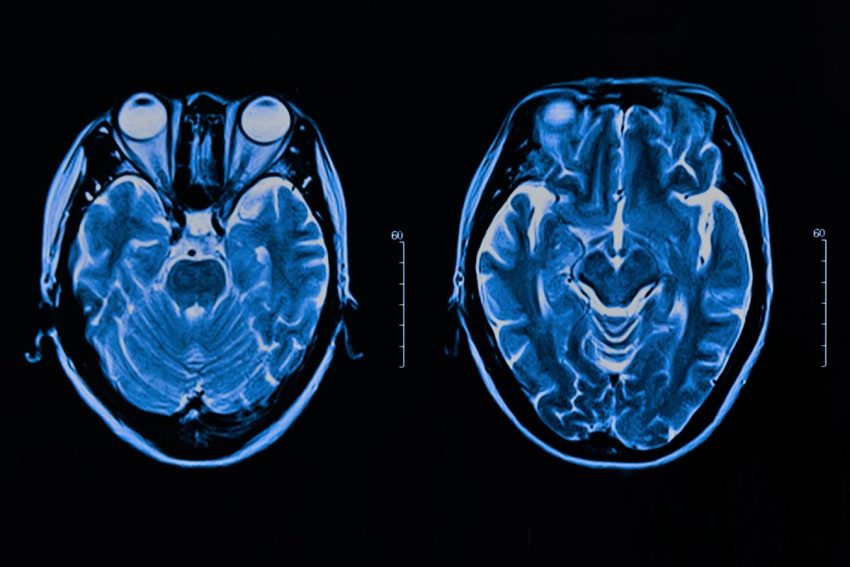

How AI could detect signs of mental illness

Researchers in Japan used artificial intelligence to analyse people’s face movements and detect subtle signs of depression